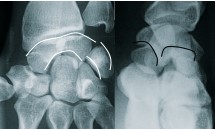

La luxation périlunaire du carpe est la luxation intracarpienne la plus fréquente dans laquelle le lunatum est le pivot. C'est une pathologie rare et grave du sujet jeune. La forme typique, mais pas la plus fréquente, est la luxation rétrolunaire...